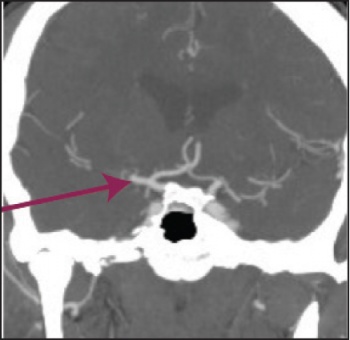

See Figures 1(i)-3(ii) for images of a successful endovascular therapy case.

Figure 1 (i): this and Figure 1(ii) show axial and coronal CT angiogram identifying proximal right MCA (M1) occlusion(click to enlarge)